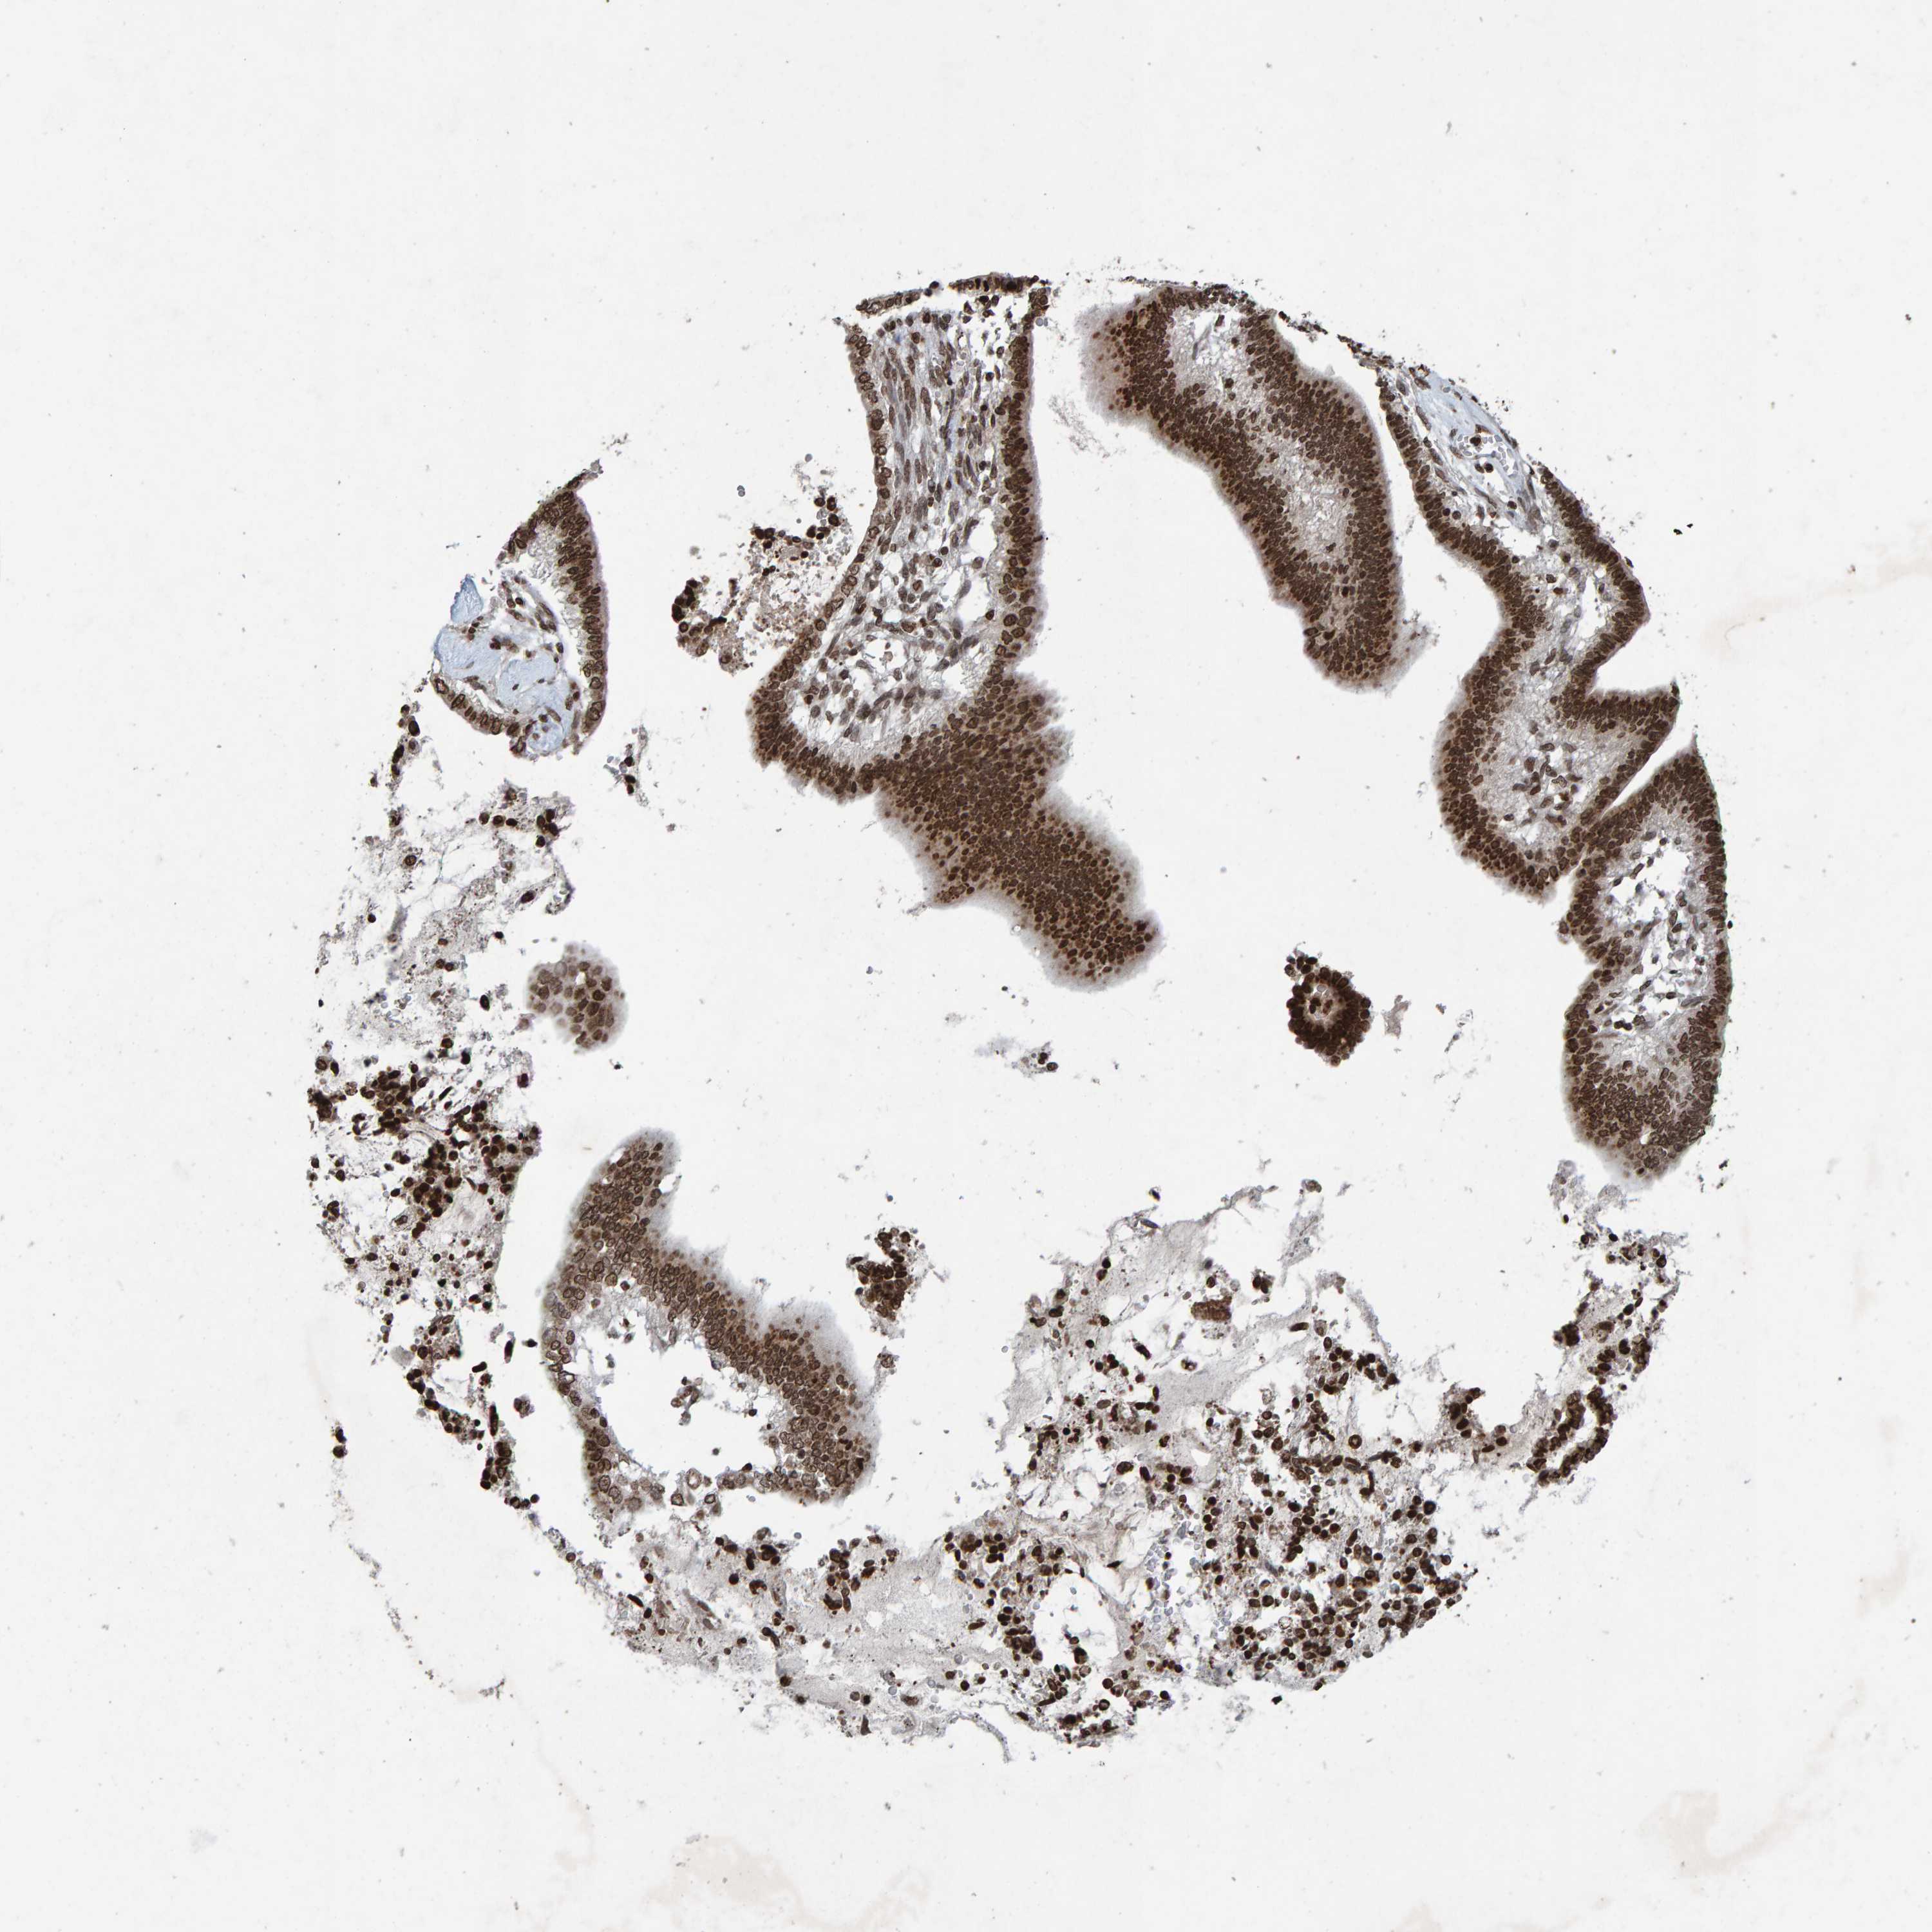

CERVICAL CANCER - Protein expressioni

A mouse-over function shows sample information and annotation data. Click on an image to view it in a full screen mode. Samples can be filtered based on level of antibody staining by selecting one or several of the following categories: high, medium, low and not detected. The assay and annotation is described here.

Note that samples used for immunohistochemistry by the Human Protein Atlas do not correspond to samples in the TCGA dataset.

Antibody stainingi

Antibody staining in the annotated cell types in the current human tissue is reported as not detected, low, medium, or high, based on conventional immunohistochemistry profiling in selected tissues. This score is based on the combination of the staining intensity and fraction of stained cells.

Each image is clickable and will lead to virtual microscopy that enables deeper exploration of all samples and also displays staining intensity scores, fraction scores and subcellular localization as well as patient and tissue information for each sample.

Antibody HPA057236

Antibody CAB022549

Staining

High

Medium

Low

Not detected

Intensity

Strong

Moderate

Weak

Negative

Quantity

>75%

75%-25%

<25%

None

Location

Nuclear

Cytoplasmic/membranous

Cytoplasmic/membranous,nuclear

Squamous cell carcinoma, NOS

Adenocarcinoma, NOS